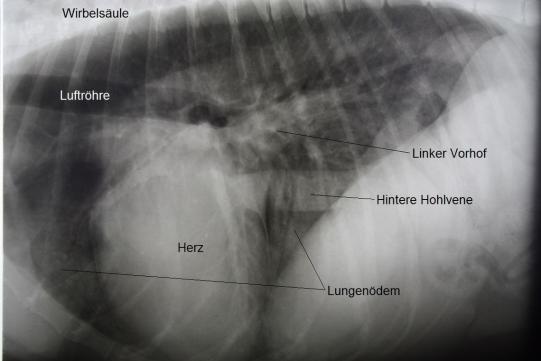

Radiologisch wird schnell klar, weshalb der Hund verstärkt atmet: Weite Teile der Lunge scheinen diffus verdichtet (d.h. weiss); Art und Verteilung der Veränderungen sprechen für eine Ansammlung von Flüssigkeit in der Lunge, ein Lungenödem. Die Herzsilhouette ist ausserdem vergrössert, insbesondere die linke Herzkammer und der linke Herzvorhof erscheinen erweitert.